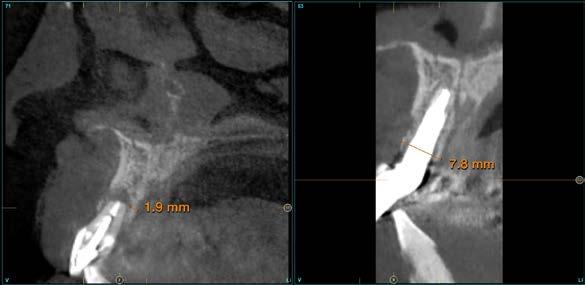

radiografía panorámica inicial para el diagnóstico nos aporta una imagen radiolucida entorno al ápice del diente en posición 11 ( Figura 1 ). Para conocer mejor el alcance de la lesión y las opciones terapéuticas de las que disponemos se lleva a cabo un cone-beam en el que se puede objetivar de forma precisa el defecto apical al diente. Este defecto es circunferencial y está dejando una reabsorción casi completa de la tabla ósea vestibular y parcial de la palatina, con un grosor de 1.9 mm, como vemos en el corte seccional (Figura 2). Si observamos la medida total en la zona media del incisivo dentral, necesitamos cubrir una anchura aproximada de 8 mm por lo que el implante que coloquemos irremediablemente dejará un gap, que según los protocolos quedará en vestibular. Utilizando una plataforma estándar de 4.1 mm el gap a rellenar será prácticamente de 4 mm según las medidas que nos

Figura 2. Corte seccional del cone-beam

arroja el cone-beam de planificación. Utilizaremos además un implante de longitud mayor que la que se emplearía para un incisivo central en una zona edéntula, para lograr un anclaje apical que nos dé la estabilidad necesaria en la colocación del implante y

nos permita la carga inmediata posterior. En este caso 11.5 mm (Figura 3 y 4).Una vez diagnosticado el caso de forma correcta con las imágenes del cone-beam iniciamos la fase quirúrgica. Realizamos la exodoncia del diente 11 con el menor trauma